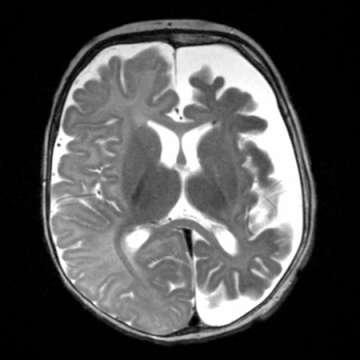

Neurologically, the infant or child may present with seizures that are progressively more difficult to control with medications. In addition, neurological deficits and developmental delay may result. Visual field defects may also occur with variable severity. Hydrocephalus (i.e. too much brain fluid) also may occur. A small proportion of patients have no neurologic abnormalities.

The reasons for neurologic progression in SWS are uncertain. One possible mechanism is the lack of blood flow and oxygen to the surrounding brain.